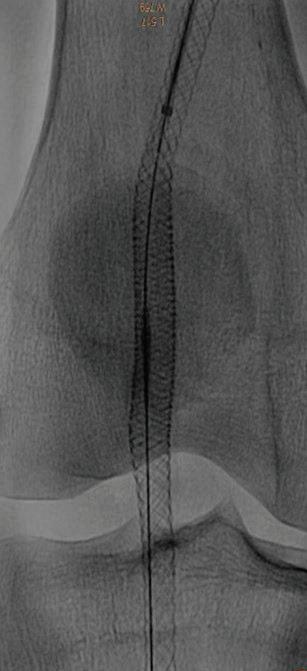

60 КЪСНА РЕВАСКУЛАРИЗАЦИЯ СЛЕД ОСТРА ТРОМБОЗА НА А. СУБКЛАВИА СИНИСТРА –КЛИНИЧЕН СЛУЧАЙ Р. Рунков

62 РЕТРОГРАДНА ПЕРКУТАННА

Лактазна неустойчивост. Състоянието (хиполактазия) е най-често срещаната физиоло -

гична причина за LI. Макар